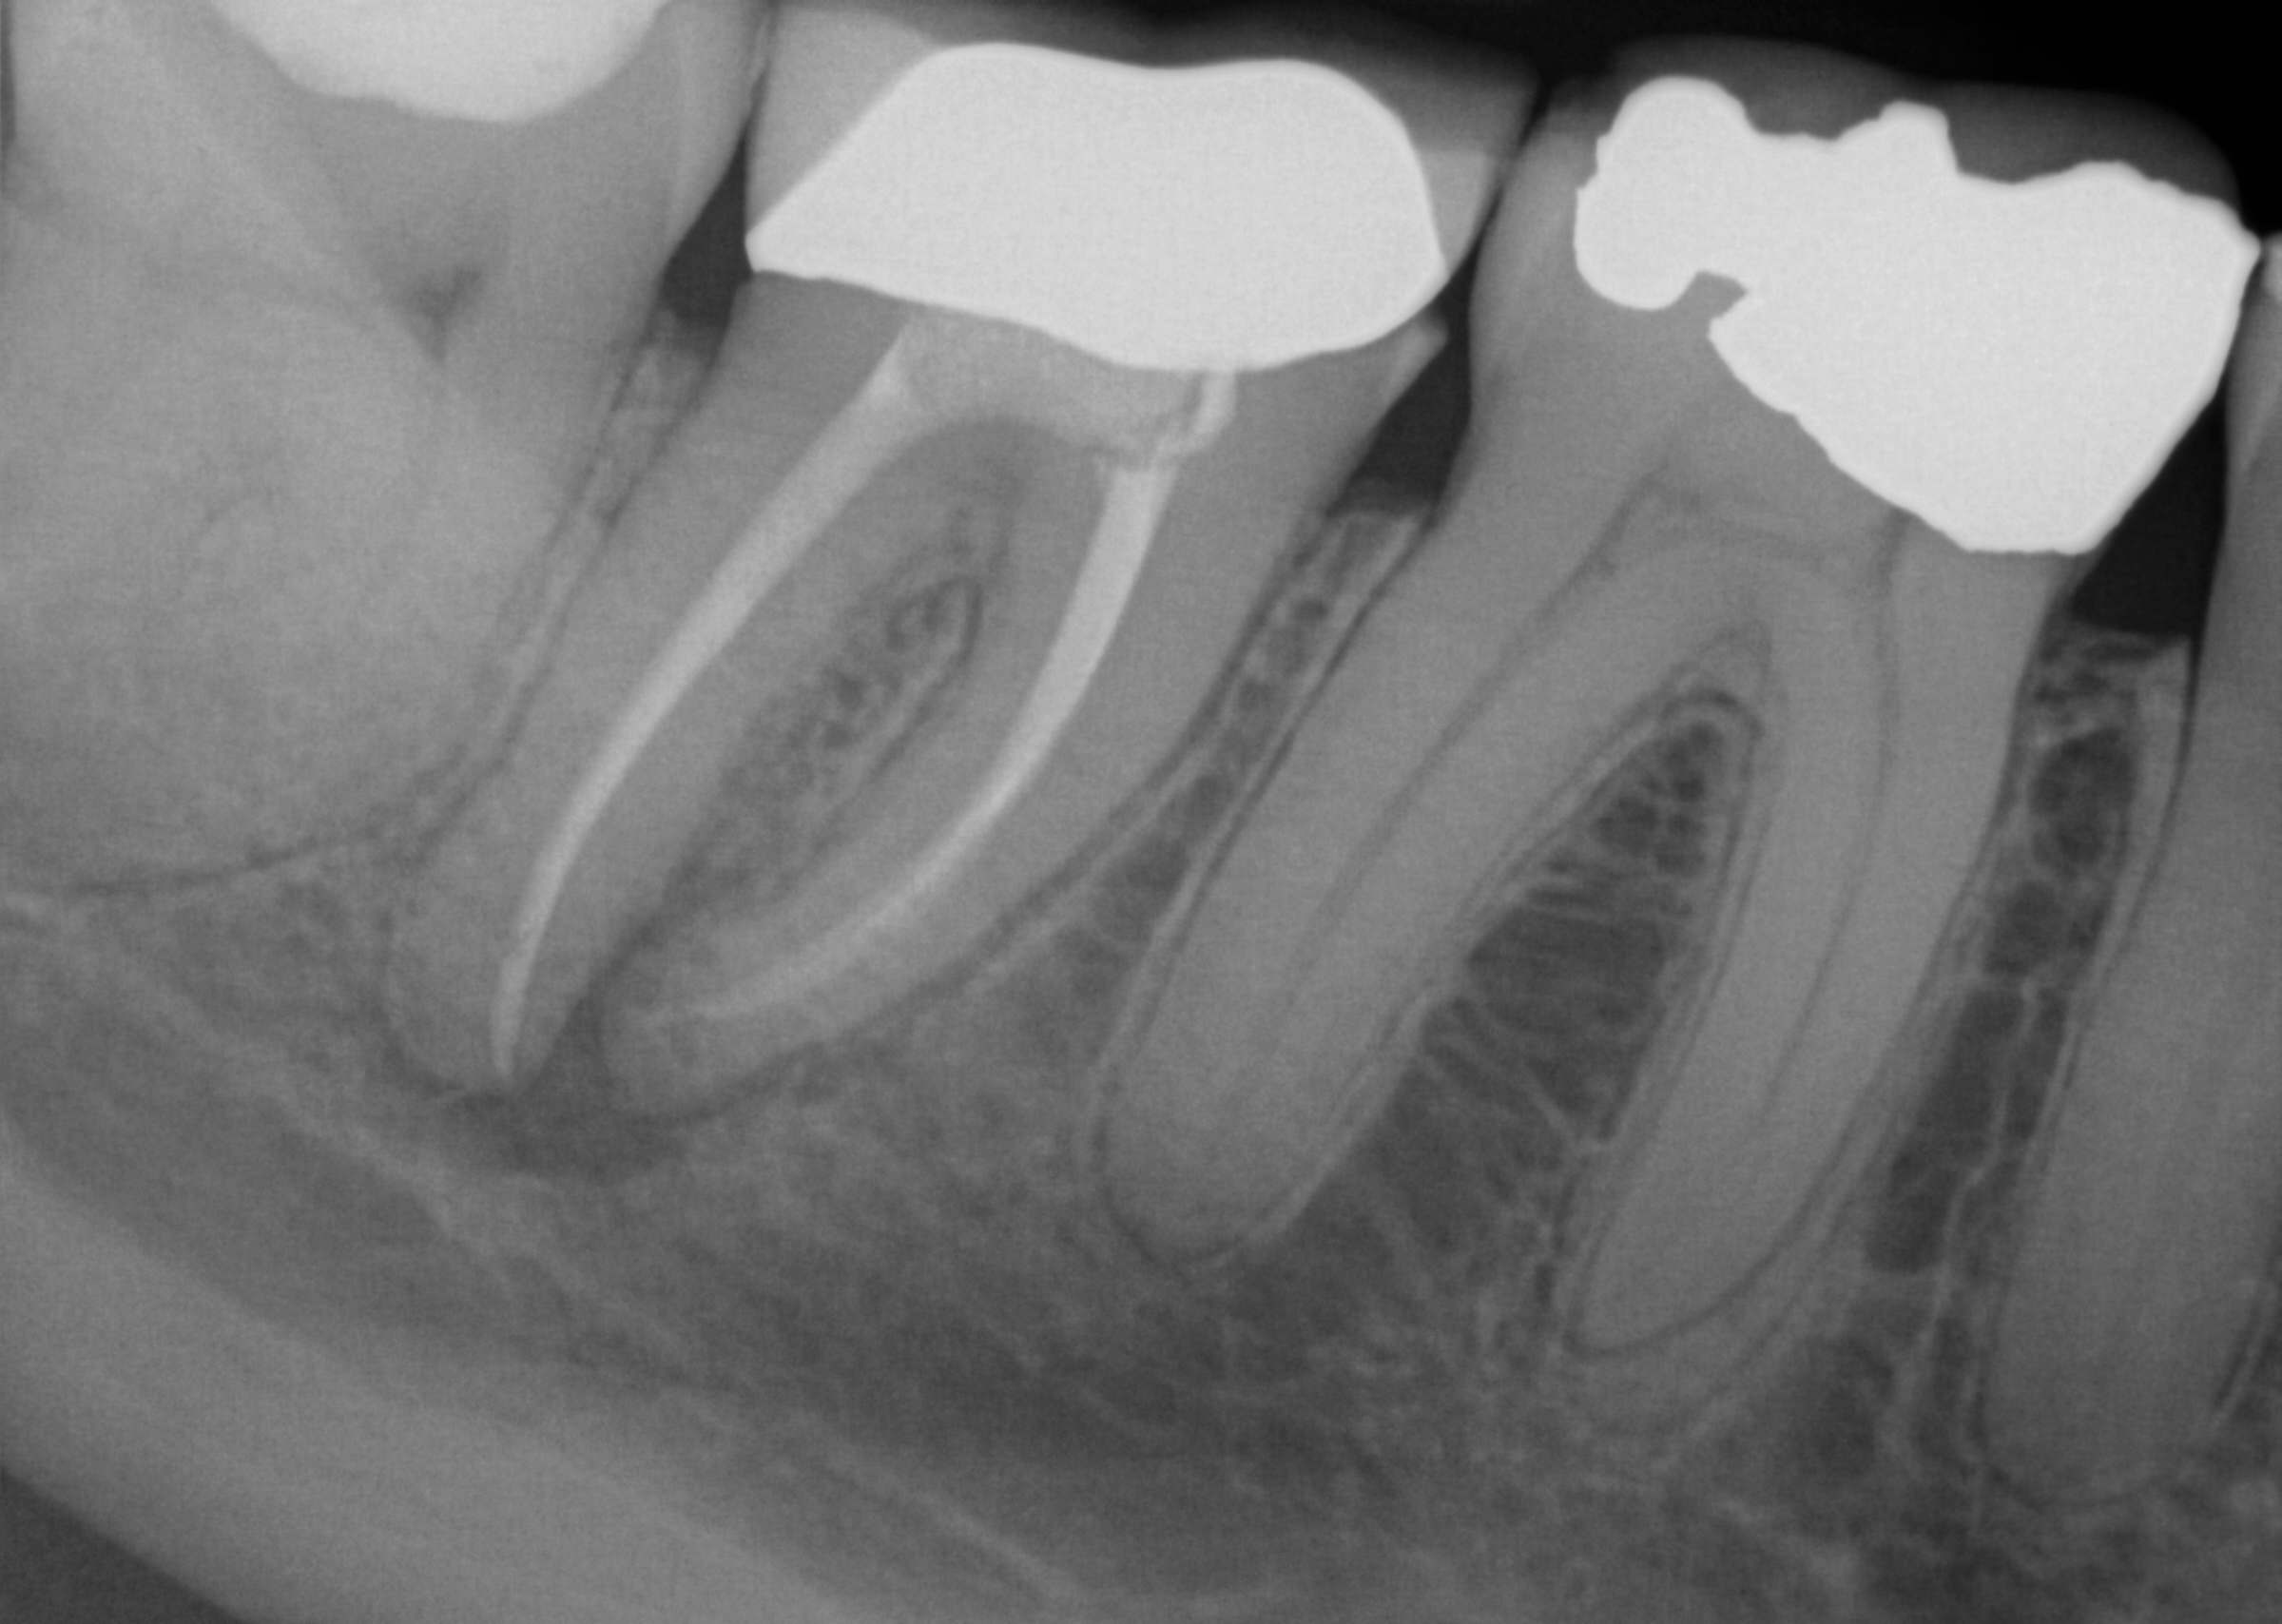

Fig 1. An implant was placed at site No. 30. Immediately after the effect of the local anesthesia subsided the patient complained of paresthesia (no pain) of the mandibular right lip and chin. A periapical radiograph taken at the time of implant placement demonstrated no apparent implant penetration into the inferior alveolar canal.

Figure 1